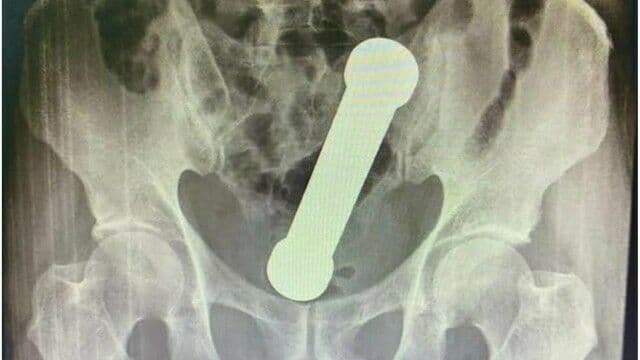

Médicos retiram peso de academia de dentro de paciente de Manaus